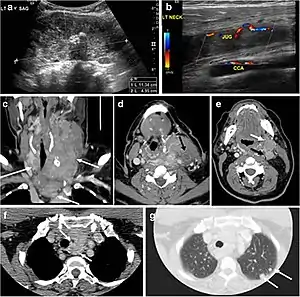

Goiter

A goiter is an abnormal thyroid gland proliferation that manifests as multi-nodular, uni-nodular, or non-nodular diffuse glandular enlargement. A goiter is formed of solid matrix, colloid cysts, blood products, calcification, and fibrosis, and this heterogeneity may lead to variable appearances on a CT scan (Figs. 13, 1414 and and15)15). The US is more sensitive in evaluating thyroid nodules within a goiter; however, a symptomatic goiter may require surgical treatment with total thyroidectomy, and in this case CT plays an additional role in preoperative evaluation. Specific aspects for examination on a CT scan during the preoperative evaluation for goiter include extension, mass effect, and suspicious features of malignancy.[1]

Fig. 13. A 27-year-old female patient known to have goiter. a, b Axial and sagittal enhanced CT scan images of the neck demonstrate a heterogeneously enhancing, enlarged thyroid gland with scattered calcifications (white arrow), cystic changes, and substantial retro-sternal extension (black asterisks). No lymphadenopathy or substantial airway narrowing.[1]

Fig. 14. A 19-year-old male patient known to have multi-nodular goiter and FNA, showing underlying Hashimoto's thyroiditis. a, b Sagittal and transverse greyscale and colour Doppler ultrasound of the neck demonstrate a hypoechoic enlarged right thyroid lobe with small hyperechoic regenerative nodules and marked hypervascularity (white arrows). c, d Enhanced axial CT scan images of the neck demonstrate a heterogeneously enhancing and enlarged thyroid gland, left more than right lobe, and the trachea is markedly narrowed.[1]

Fig. 15. A 33-year-old female patient who presented with neck swelling and pain and was later diagnosed with Hashimoto's thyroiditis. an Axial enhanced CT scan of the neck demonstrates minimal diffuse enlargement of the thyroid gland, especially the isthmus (white arrow). b Transverse greyscale ultrasound of the neck demonstrates heterogeneously enlarged thyroid and thickened isthmus, measuring 8.6 mm.[1]

Malignancy can coexist within the goiter and a CT scan may give a clue if there are abnormal cervical lymph nodes and/or signs of invasion. Retrosternal extension (Fig. 15) could affect the surgical approach, as a lower extent may require a partial or total sternotomy to facilitate complete resection. Therefore, the distance of the retrosternal extent from the sternal notch should be measured on a sagittal image.[1]

The interpreting radiologist should describe the mass effect, detailing its degree and direction of displacement of central structures, including the trachea, oesophagus, larynx, and pharynx. Attention should be directed to the upper extent of the goiter and structures immediately surrounding the thyroid gland, including the neuro-vascular structures, retropharyngeal space, and pre-vertebral space. The reporting radiologist should evaluate the vocal cords for symmetry and signs of vocal cord palsy.[1]